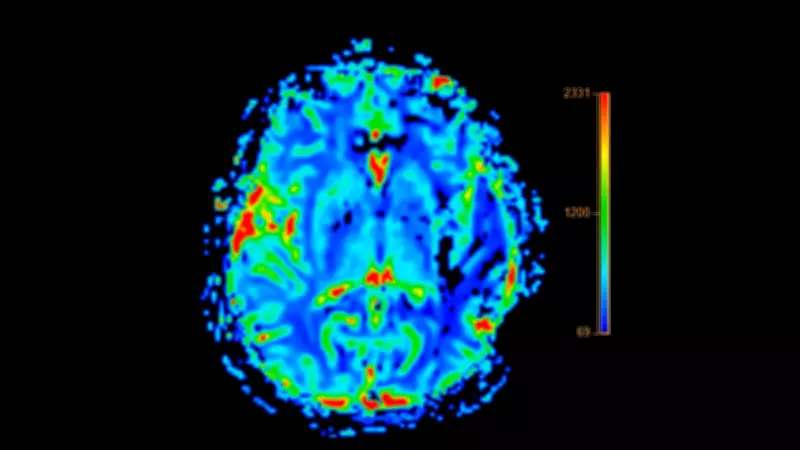

Yapay zeka teknolojisi, insan gözünün fark edemeyeceği kadar küçük anatomik değişimleri saniyeler içinde analiz ederek Alzheimer'ın erken belirtilerini ortaya çıkarıyor. Araştırmacılar, yaşları 69 ile 84 arasında değişen yüzlerce kişiden alınan 800'den fazla MR taramasını bu gelişmiş algoritmaya emanet etti.

Algoritma, beynin 200 farklı bölgesini detaylı bir şekilde tarayarak mikro düzeydeki değişiklikleri mercek altına aldı. Analizler sonucunda özellikle üç kritik bölgedeki hacim kayıplarının hastalığın en güçlü habercileri olduğu kanıtlandı:

- Hipokampus: Hafızanın merkezi olarak bilinen bu bölgedeki değişimler

- Amigdala: Duyguların işlendiği alandaki anatomik farklılıklar

- Entorhinal korteks: Zaman algısını yöneten bölgedeki hacim kayıpları